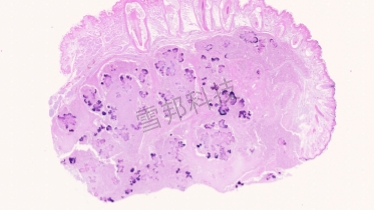

革兰氏染色是用来鉴别细菌的一种方法,细菌细胞壁上的主要成份不同,利用这种染色法,可将细菌分成两大类,即革兰氏阳性菌与革兰氏阴性菌。革兰氏染色的对象是细菌的细胞壁,染色后细菌与环境形成鲜明对比,可以清楚地观察到细菌的形态、排列及某些结构特征,而用以分类鉴定。